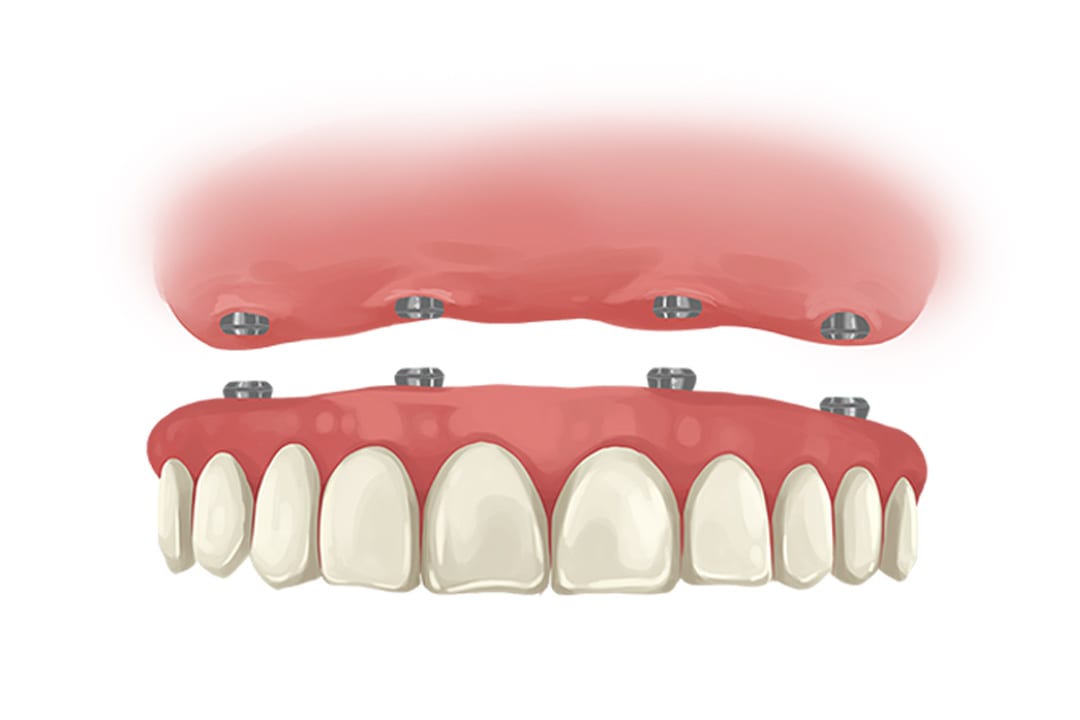

Dental Implant Overdenture

For patients who are edentulous and missing all of their teeth, an implant supported denture may be a viable solution as well, this procedure replaces all missing teeth by utilising a couple of implants to retain or support a denture.

Since dental implants are inserted directly into the jawbone, implant retained/supported dentures are a lot comfortable than regular dentures and almost immovable, making biting and chewing feel as natural as possible.

All On 4 Dental Implants

All On 4 dental implants offer a modern solution for individuals who have lost most or all of their teeth. This technique involves surgically placing four implants in the jaw, which act as anchors for a full arch of prosthetic teeth.

Unlike traditional implants, four implants are typically angled to enhance stability and make efficient use of the existing bone, often eliminating the need for bone grafting. This method is particularly beneficial for patients with significant bone loss who may not be candidates for conventional implants.

One of the most significant advantages of All On 4 dental implants is the possibility of immediate loading, allowing patients to receive a full set of temporary teeth on the same day as the surgery. This immediate functionality, combined with a high success rate and the potential for a lifelong tooth loss solution, makes All On 4 a popular choice.